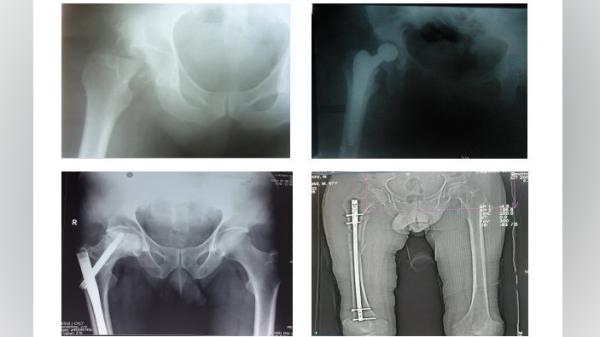

Кандидат медицинских наук Таджикистана Давронджон Махмудов представил доклад «Оптимизация профилактики венозных тромбоэмболических осложнений — при проблемах длинных костей нижней конечности».

Как он отметил в своем докладе, венозные тромбоэмболические осложнения, к котором относятся тромбоэмболия лёгочной артерии, тромбоз глубоких вен, тромбофлебит подкожных вен, являются одной из наиболее актуальных проблем современной медицины.

По данным ВОЗ, ромбоэмболия лёгочной артерии явилась непосредственной причиной смерти каждого четвёртого умершего больного с повреждениями опорной двигательного аппарата и среди них преобладают пациенты с травмами бедра, таза, костей голени и сочетанные травм.

При этом, докладчик отмечает, что точная своевременная диагностика тромбоза глубоких вен на основе клинических симптомов затруднена, а применение дополнительных методов исследования не всегда возможно. Подавляющее большинство случаев тромбоза глубоких вен в посттравматическом и послеоперационном периодах не имеют ярких клинических проявлений. Поэтому, учитывая данные исследований, с практической точки зрения можно считать, что развитие тромбоза глубоких вен в дистальных отделах голени при повреждениях и оперативном лечении нижних конечностей, таза, сочетанной травме и постельном режиме больного, является закономерностью.